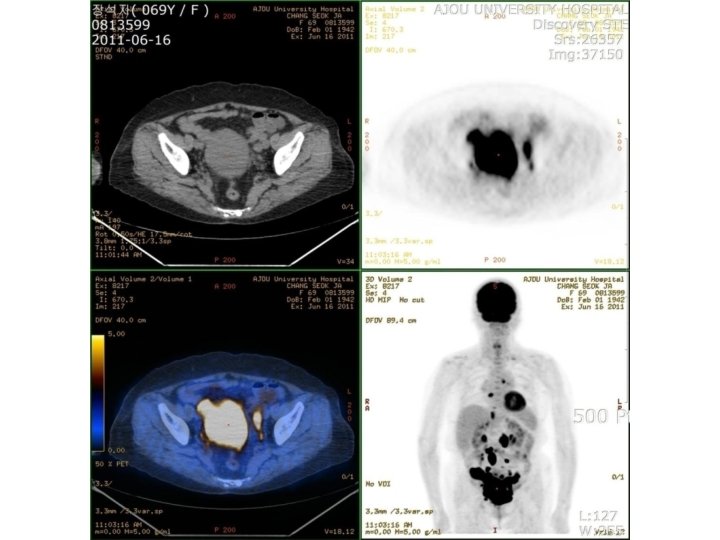

Discussion • Less than 1% of extranodal lymphomas arise from gynecologic tract. 7~30% of secondary involvement. • 23~30% sensitivity of conventional Pap smear • More challenging on liquid preparations

Hyperchromatic cells with high N/C ratio on Pap smear 1. Long list of differential

Hyperchromatic cells with high N/C ratio on Pap smear 1. Long list of differential diagnosis benign/reactive, preneoplastic, and neoplastic process 2. Careful systematic evaluation of squamous and glandular elements as well as the background component 3. Correlation with clinical history and radiological findings